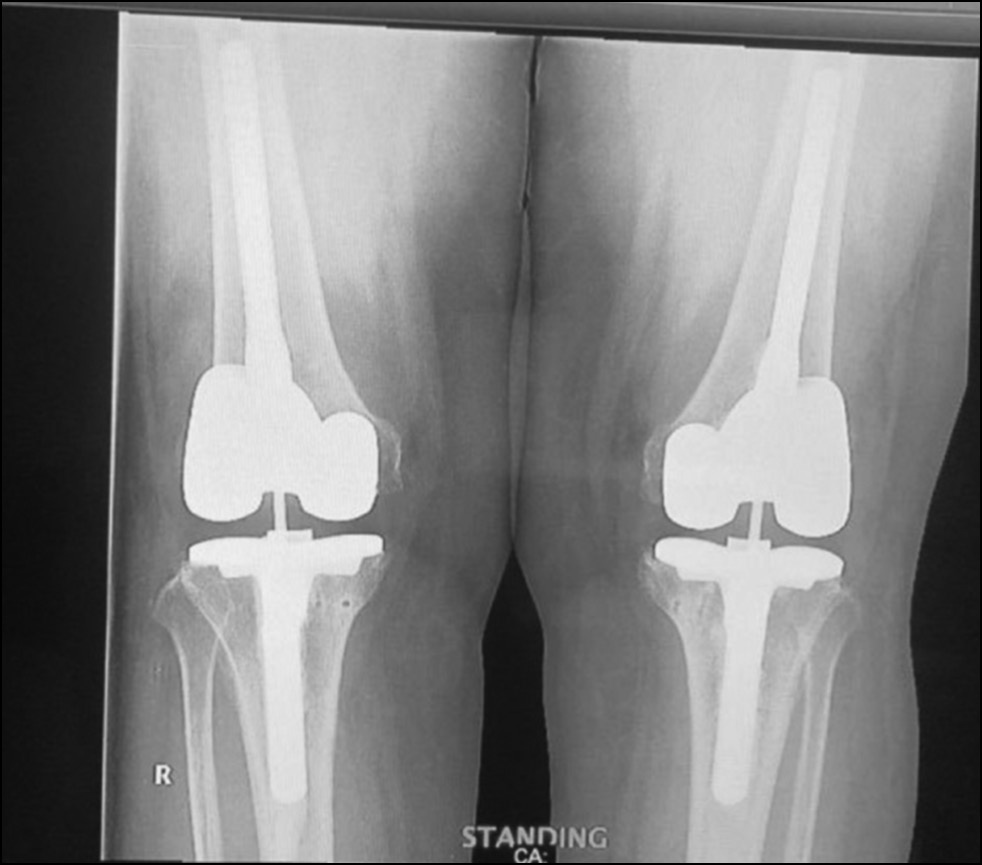

Radiological assessment (Fig. 11–14)

Fig. 13. Ap postoperative x-ray showing bilateral total knee arthroplasty.

Рис. 13. Послеоперационная рентгенограмма с двусторонней тотальной артропластикой коленного сустава.

Fig. 14. Lateral postoperative x-ray right and left knees showing bilateral total knee arthroplasty.

Рис. 14. Послеоперационная боковая рентгенограмма правого и левого колена, демонстрирующая двустороннюю тотальную артропластику коленного сустава.